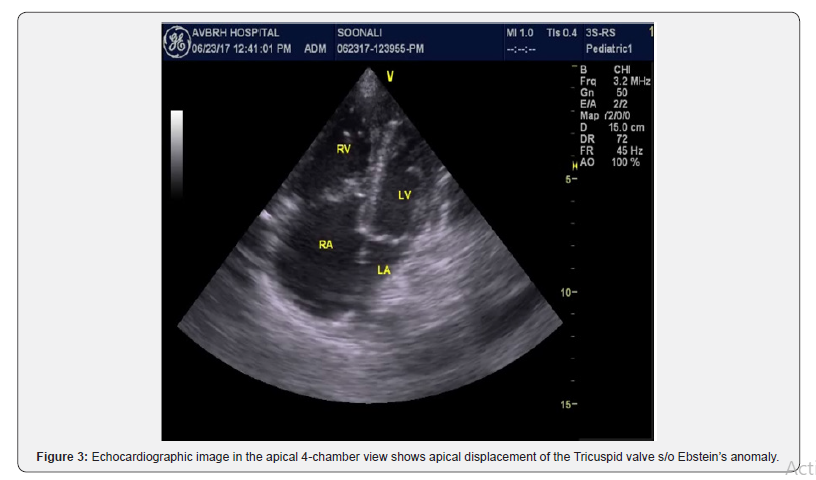

The chest X-ray documented cardiomegaly due to enlargement of the right cardiac chambers. ECG shows right axis deviation with right atrial enlargement and wide QRS complex. Echocardiography was done to rule out any underlying congenital cyanotic heart disease, which was suggestive of Ebstein’s anomaly with large size Ostium Secundum type of Atrial Septal Defect with mild Tricuspid Regurgitation (Figure 3). Repeat CT brain with contrast was done on 18th day of illness to see the size of abscess which revealed no improvement despite of administration of higher antibiotics for over 7 days. Then patient was taken for surgery by neurosurgeon and drained the abscess. A right parietal craniotomy, excision and evacuation of abscess were done under general anaesthesia. Abscess with thick capsule was seen and thick yellowish pus was drained and sent for culture. The repeat CT scan after operation, showed minimal edema. After receiving total 4 week of antibiotics, patient was discharged with no neurological problem.

In our case, EA was diagnosed which is a rare and complex congenital cardiac malformation. The pathological changes of EA are that septal, posterior and anterior leaflet of tricuspid valve are not adhere to tricuspid annulus which move down to RV spirally with textural anomalies and paramorphia of atrioventricular sulcus, valve, flap structure, and RV. However, clinical manifestations depend on the structural and functional alterations in the right cardiac chambers as well as in tricuspid valve morphology, and are more severe the greater the displacement of leaflet insertion. In the presence of septal defect, the increased right atrial pressure induced by the hemodynamic and functional changes resulting from EA cause reversed shunting (right-to-left), which is an anatomical substrate for paradoxical embolism that can lead to in stroke [10-12].